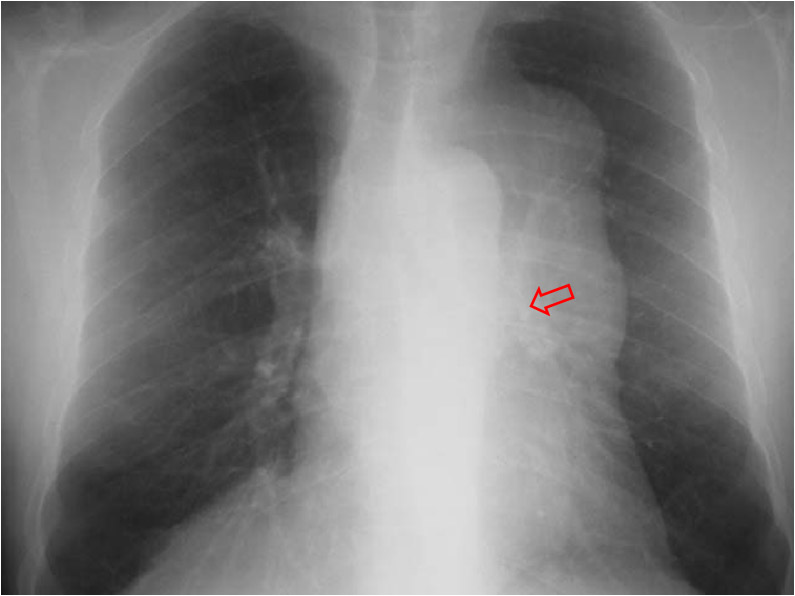

Otro ejemplo del signo del hilio tapado, esta vez correspondiente a un carcinoma tímico superpuesto al hilio izquierdo (flecha).